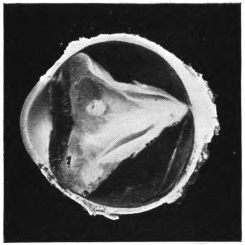

PLATE IV.

22.

LENS DISLOCATED BEHIND RETINA

curly bracket span

48

23.

FISTULA OF THE CORNEA

24.

CAPSULO-CORNEAL SYNECHIA

25.

RETINO-CORNEAL SYNECHIA

26.

SCLERAL FISTULA

27.

"    " (MAGNIFIED)